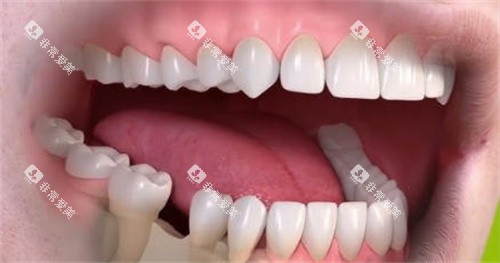

固定桥,又称固定义齿,通过将假牙固定在两侧邻牙上实现修复,是目前较为常见的修复方式。

固定桥主要优点是舒适度高、异物感小,无需摘戴,使用方便,咀嚼效率也高于活动义齿。但其显著缺点是需要磨损邻牙作为基牙,对健康邻牙造成不可逆损伤。同时,桥体与牙龈之间容易食物嵌塞,可能导致基牙龋坏或牙周问题。

固定桥适合邻牙健康(或有较大充填物需保护)、缺牙区间隙适中、牙槽嵴条件良好且经济预算中等的患者。这是介于活动义齿和种植牙之间的折中选择。